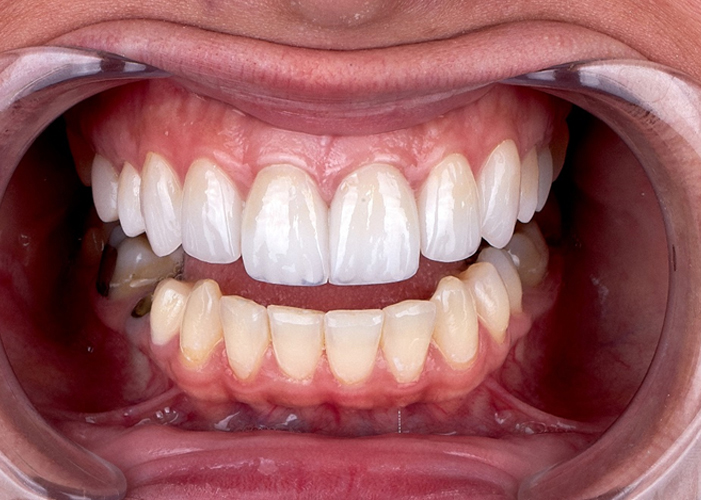

전악 임플란트

치아가 하나도 없거나 심각한 구강질환을 앓고 있어도

전악 보철을 제작, 임플란트를 치조골에 식립해

기능적, 심미적으로 자연치아와 가장 유사한 수준으로 재현이 가능합니다.

건강보험으로 걱정 없이 치료 받으세요!지르코니아 보철 임플란트

경제적인 부담으로 망설이고 계셨다면 걱정하지 마세요.

건강보험에 가입되어 있는 만 65세 이상 환자분의 경우,

위치 상관없이 평생 2개까지 본인 부담금 30%만 부담 하시면

기존 PFM 보철보다 더 튼튼한 지르코니아 적용이 가능합니다.